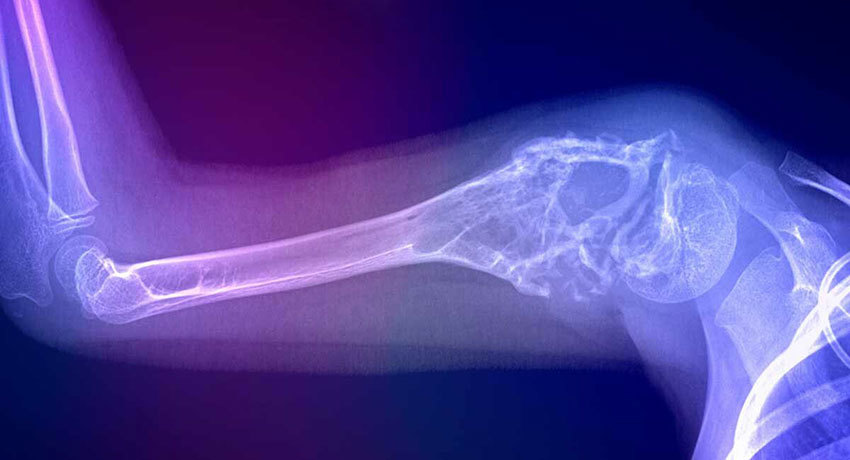

Хирургическое лечение

Локальное лечение саркомы Юинга должно быть проведено не позднее 2–3 недель после завершения курса индукционной химиотерапии. В последние 10–15 лет существенно расширились возможности органосохраняющих операций. Вопрос о возможности хирургического вмешательства, его оптимальном виде и объеме обсуждается на врачебном консилиуме с участием онколога, хирурга-ортопеда и других специалистов.

При саркомах костей конечностей в ряде случаев может быть выполнено органосохраняющее вмешательство. Удаленную костную ткань замещают трансплантатом из других частей тела или искусственным протезом. Если опухоль расположена близко к суставу, выполняют его эндопротезирование. К ампутациям конечностей современные хирурги стараются прибегать только в крайних случаях, когда органосохраняющая операция объективно невозможна.